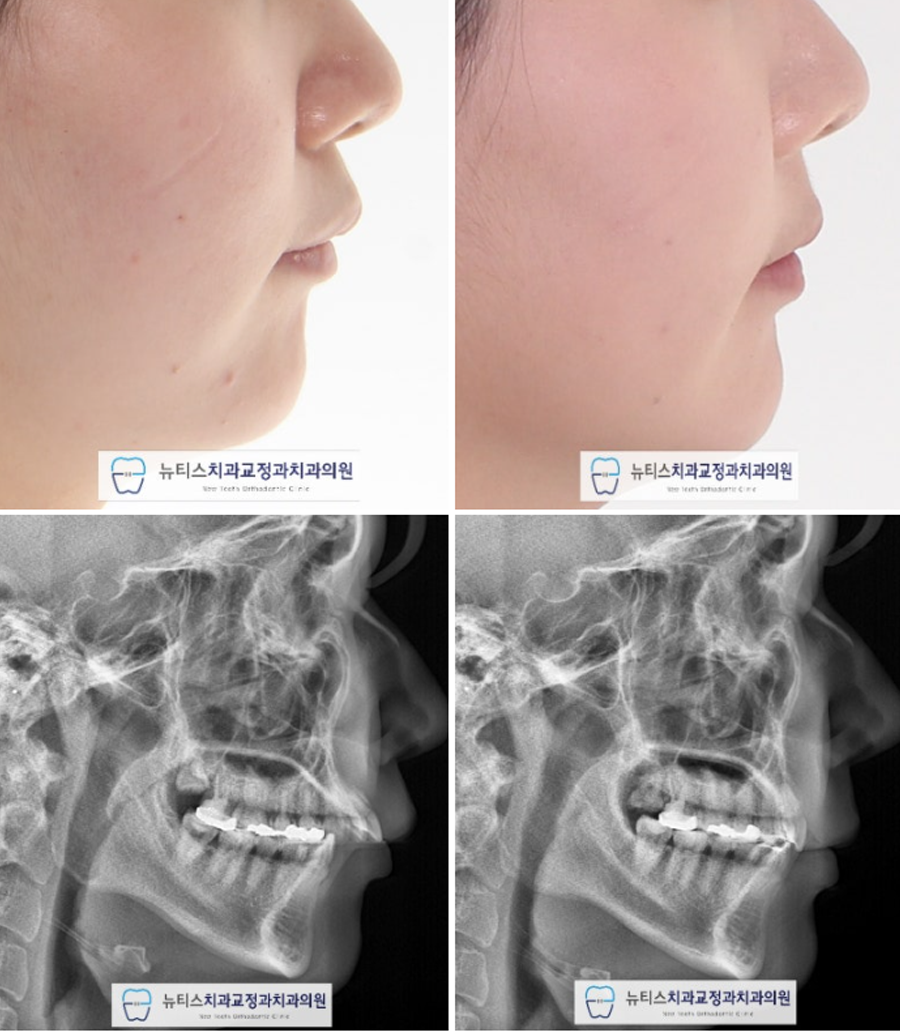

Ãø¸ð ¾È¸ð ¹× ¹æ»ç¼± »çÁøÀÔ´Ï´Ù.

µ¹ÃâµÈ ¾Õ´Ï°¡ µé¾î¿À¸é¼

µ¹ÃâÀÔµµ °³¼±µÇ¾ú½À´Ï´Ù.

Ä¡·á±â°£ : 1³â 9°³¿ù